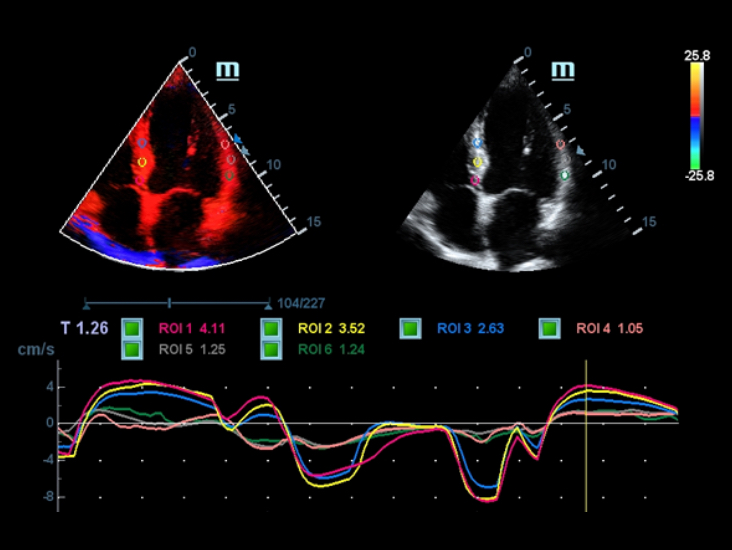

Volle Palette der Anwendungstools: Genauigkeitsgarantie mit bequemem iTouch

DC-40 mit Full HD bietet viele Tools zur bequemen Maximierung der diagnostischen Genauigkeit. Das DC-40 mit Full HD deckt die allgemeine Bildgebung, die Obstretik/Gyn?kologie sowie die Kardiologie ab und bietet damit eine Komplettl?sung f├╝r die wichtigsten klinischen Bereiche, mit vereinfachtem Workflow f├╝r mehr Effizienz.

Smart Track

Smart Track bietet eine schnelle und intelligente Optimierung f├╝r die vaskul?re Bildgebung mit einer einfachen One-Touch-Aktion. Es kann Farbe, Leistung und das PW-Spektrum optimieren durch Self-Tracking und zeitintensivere Schritt reduzieren. Deshalb ist der Workflow der vaskul?ren Untersuchen mit einer optimalen Ansicht vereinfacht.